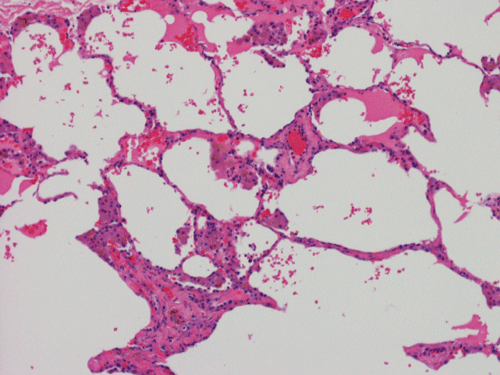

At scanning magnification (Panel A), the lung parenchyma is replaced by some coalescing fibrous nodules. The degree of involvement is variable at different fragments (Panel B and C). In the less affected areas, there are some fibrotic thickening of the septa (Panel C). In some areas, the changes are minimal and the pleural appear to be uninvolved (Panel D and E). In low to medium magnifications, these nodules of fibrosis contains a large number of hemosiderin laden macrophages (Panel F and G) admixed with fibrous tissue. The diagnostic tissue, however, is present in areas with increased cellularity. In these areas, there is a background of cells with a moderate amount of cytoplasm and bland nuclei. Some of these nuclei have kidney shape (arrow in Panel H). In some areas, many of the nuclei have a deep nuclear groove that resemble a coffee bean (arrow in Panel I). In the third type of areas, the nuclear grooving is not distinct (Panel J). Prominent eosinophilic infiltrations are almost always present. Immunohistochemistry on CD1a revealed many positive cells (Panel L). Also present in the specimen are multiple small blood vessels with thickened intima (Panel K). A Movat pentachrome stain demonstrates an internal elastic layer in these vessels and confirms that these are arteries (Panel M and N).

In the early stage of PLCH, there are interstitial infiltrates composed of LCs, lymphocytes, macrophages, eosinophils, plasma cells and fibroblasts 4. The infiltrates enlarge to form nodules centered on the small airways. Brown pigmented macrophages (smokers macrophages) are present in and around the nodules. Eosinophils tend to localize at the innermost layer of the nodules, where LCs can be most easily found in the thickened interstitium. Associated patchy interstitial and airspace organization or respiratory bronchiolitis may be present. Other smoking related changes are also common. Cavitation often occurs within the nodules which represents either an airway remenant or de novo cavitation as the inflammatory infiltrate enlarges. There is centripetal replacement of the nodules by fibroblasts which produce the classic stellate lesions of PLCH. As the disease progresses, the number of nodules, cavitary granulomas and fibrotic scars increase in number.

In the end stage, the exhausted lesions are predominantly fibrotic and largely depleted of LCs. In some regions, the fibrosis may surround cystic spaces of variable diameter to form large areas of honeycombing. This is especially predominant in the upper lobes. In cases where parenchymal scaring is present, the pulmonary function will be largely compromised. At this stage, both pulmonary function tests and radiologic findings may suggest diffuse lung disease, but biopsy will show stellate fibrotic lesions centered on the terminal airways with no identifiable interstitial inflammation. Pulmonary vasculopathy (in areas of lung remote from parenchymal nodules) is also seen in late stage PLCH. Vasculopathy manifests as intimal fibrosis, medial hypertrophy or luminal obliteration involving both venules and arteries. This may account for pulmonary hypertension seen late in PLCH.